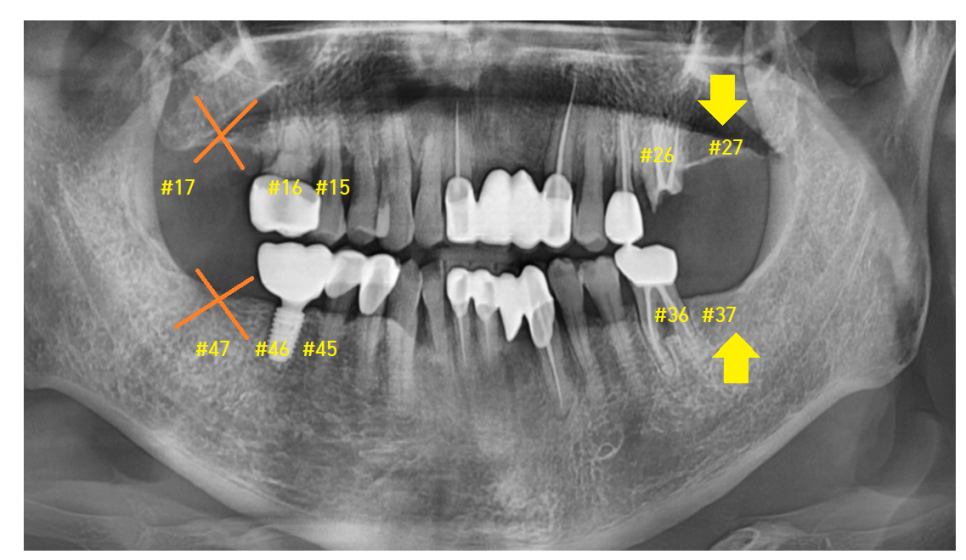

마지막 세 번째 케이스를 볼까요~?

3️⃣위아래 맨 끝 치아가

짝꿍으로 없다

23.08.07

사진 속 환자분을 보겠습니다.

오른쪽 치아도 맨 끝 치아가 위아래로 발치된 상황

왼쪽도 맨 끝 위아래가 없으시네요~

23.11.04

이럴 경우에는 환자분 결정에 맡깁니다.

교과서적으로는 치아가 상실되면

개수대로 심으면 제일 좋겠지만

환자분 상황에 맞춰 심는 게 제일 좋은 치료라 생각합니다.

치아 개수가 부족하다 보니

씹는 힘은 약하겠지만

생활이 안될 정도는 아닙니다.

#27,37 위아래로 치아가 없는 경우에는

양쪽으로 물리는 게 없어서

환자분 결정에 맡깁니다.

23.12.28

#36 왼쪽 아래 맞물리는 #26 왼쪽 위에 치아만

심는 것으로 치료를 종결